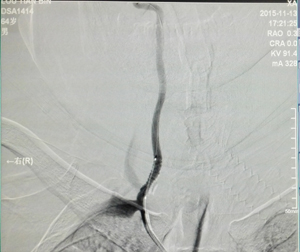

图为左侧椎动脉起始段狭窄手术后DSA 图为右侧椎动脉起始段狭窄手术后DSA 拷贝